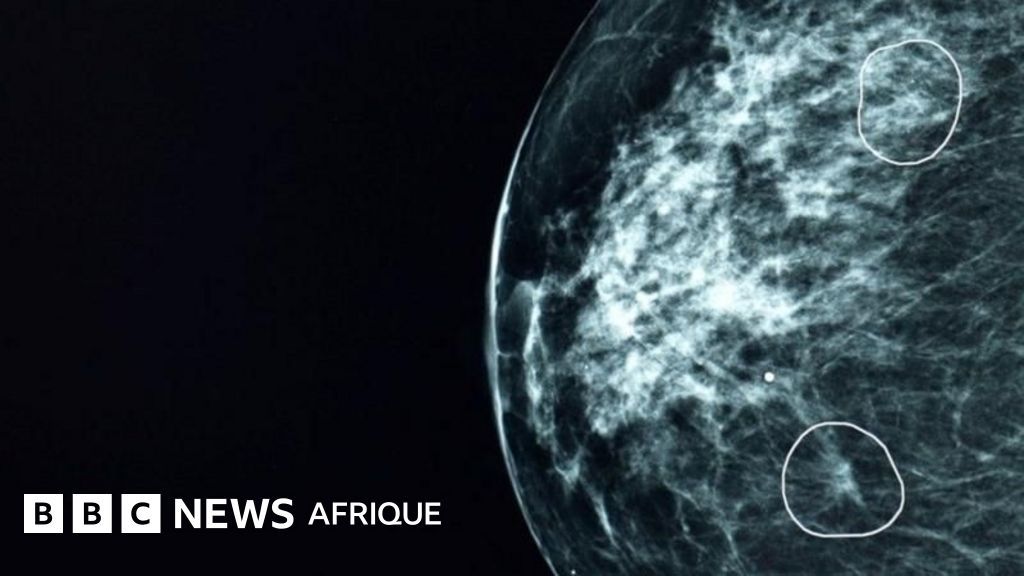

In this week’s “Let’s Talk AI” (Week 13), discover the potential impact of AI on environmental conservation. Explore how artificial intelligence technologies can detect cancerous tumors that doctors might overlook. Delve into the opportunities AI offers in the agri-food sector.